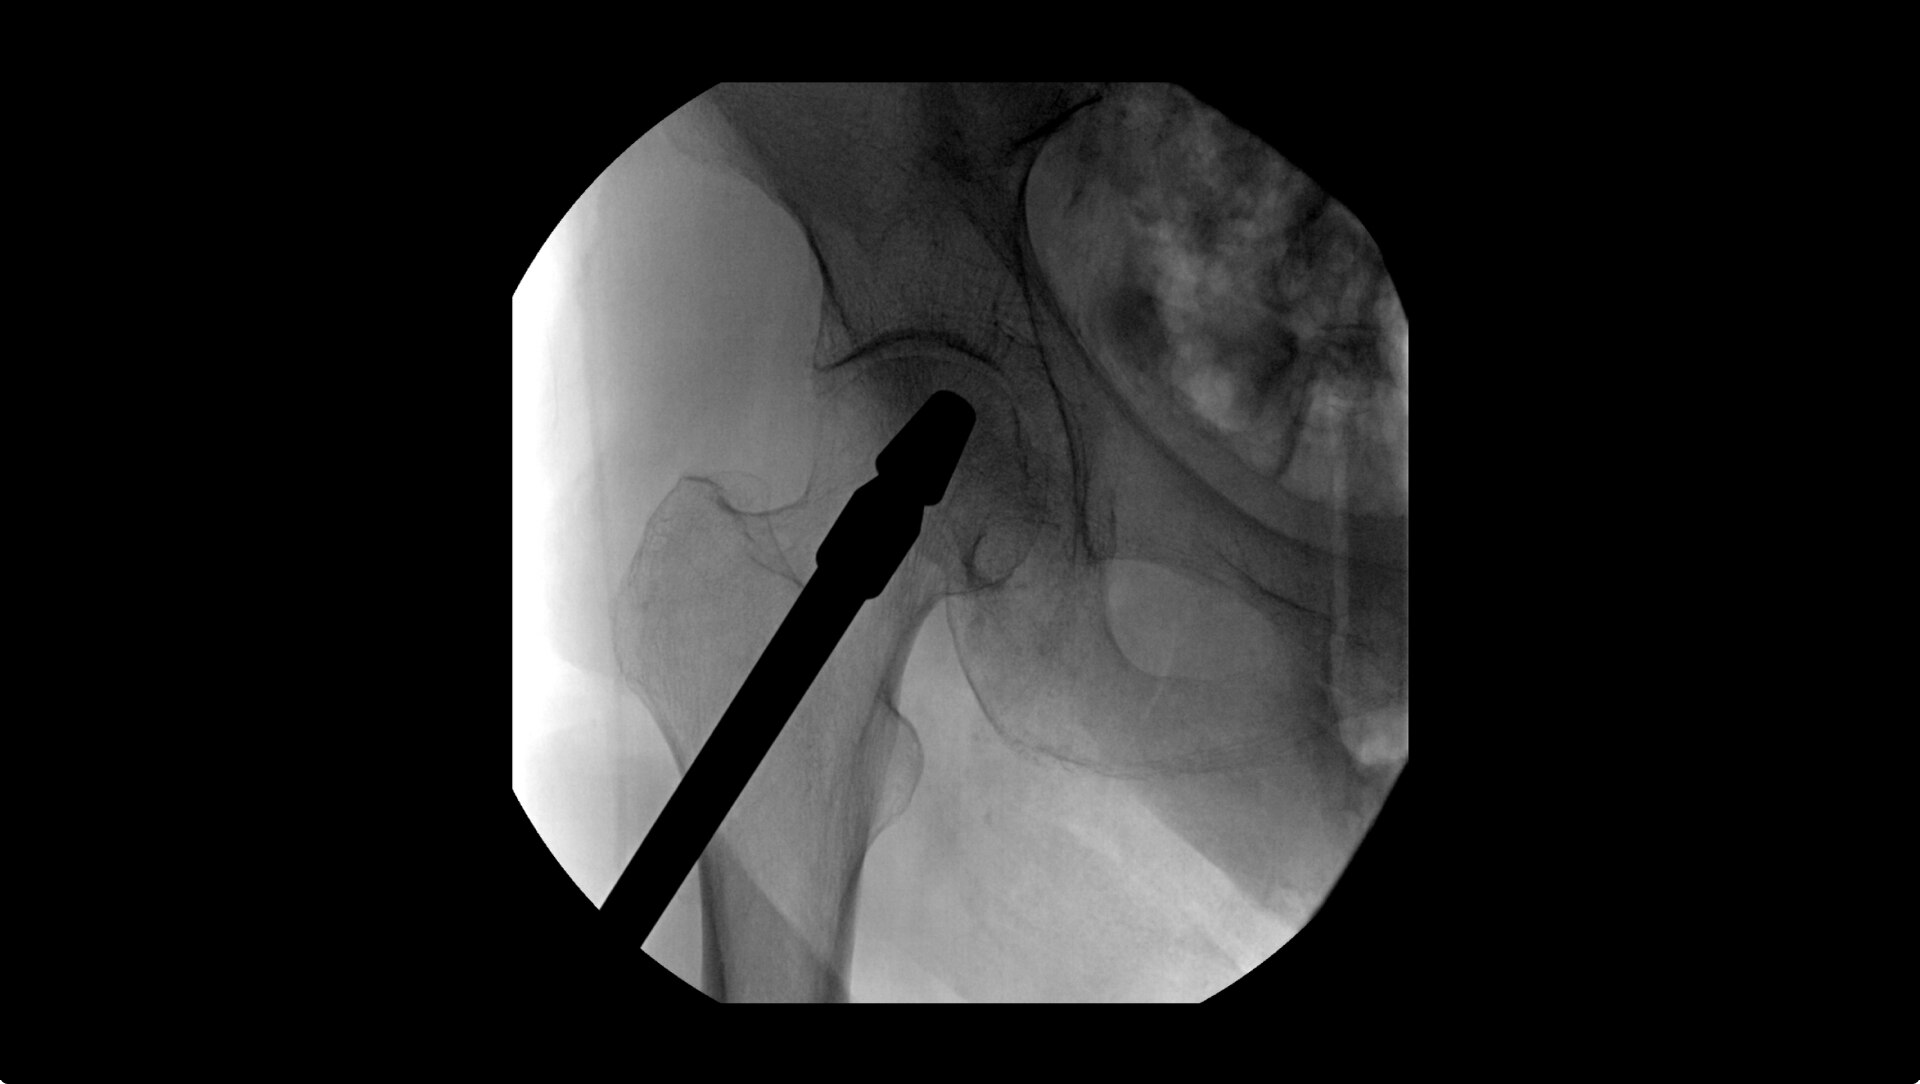

OEC C-arms provide orthopedic imaging with a large field of view optimized to clearly visualize orthopedic anatomy, such as the entire long bone femur or minute fractures in extremities. A clear display with comfortable viewing can easily show AP and lateral views, enabling efficient procedure planning.

Mark right on the image displayed with Digital Pen, to template femoral and acetabular procedures and utilize measurement and angle tools for adding references for surgical planning.

Live Zoom up to 4X during a fluoro without the additional dose of Mag modes to assess orthopedic fractures and fixations.

During hip or femur imaging, capture up to 22% more Field of View by positioning detector closer to patient anatomy with the OEC low-profile X-ray tube housing compared to mono-block C-arms.

Complex orthopedic procedures require powerful imaging systems. OEC premium C-arms perform in a variety of procedures such as:

• Hip fracture fixation

• Hip replacement